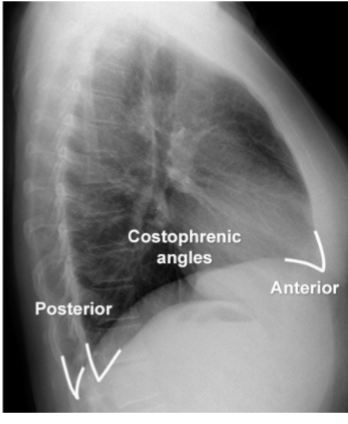

Identify costophrenic angles (post + ant)

yes